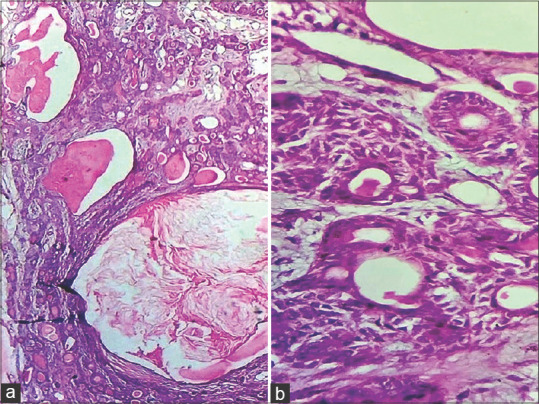

多形性腺瘤是大、小唾液腺最常见的良性肿瘤。组织学多样性是多形性腺瘤的特征。广泛的鳞状皮化生伴角蛋白填充的囊肿很少报道。我们在此报告两例涎腺多形性腺瘤伴增生鳞状化生及角蛋白填充囊肿的病例,并讨论其潜在的诊断缺陷。

Pleomorphic adenoma is the most common benign tumour of major or minor salivary glands. Histological diversity is the hallmark of pleomorphic adenoma. Extensive squamous metaplasia with keratin-filled cysts is rarely reported. Here we present two cases of pleomorphic adenoma with exuberant squamous metaplasia and keratin filled cysts formation in a minor salivary gland and discuss its potential diagnostic pitfalls.